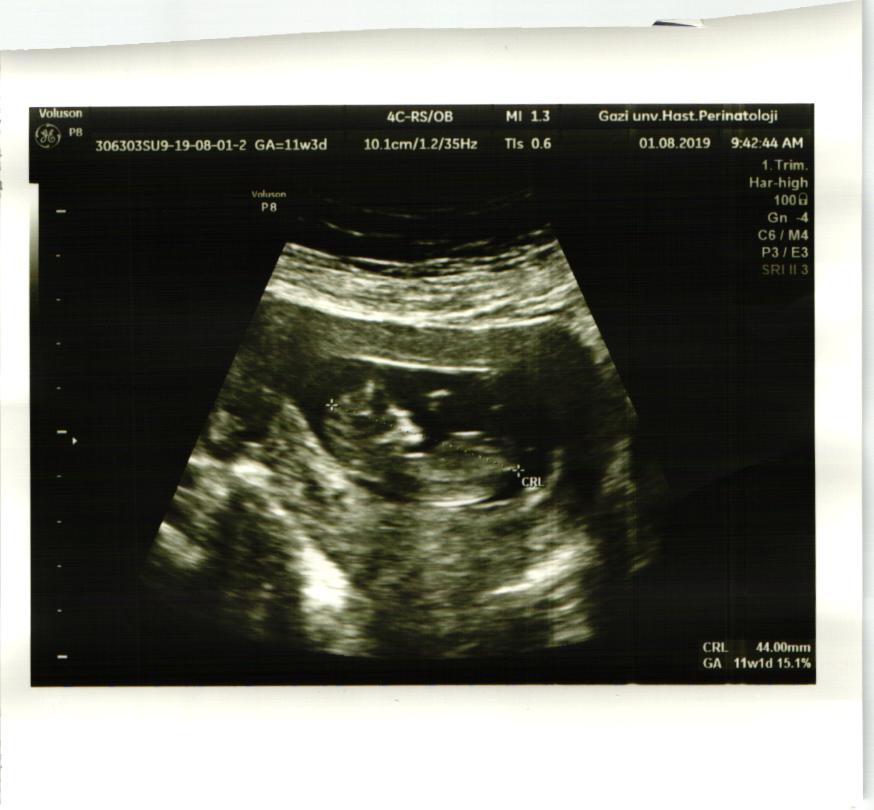

Tamam teşekkür ederim yinede elimde usg yok 11+5 haftalık nub belli olurmu o zaman

Bakabilirmisiniz nub belli oluyormu cinsiyeti nedir bebeğimin